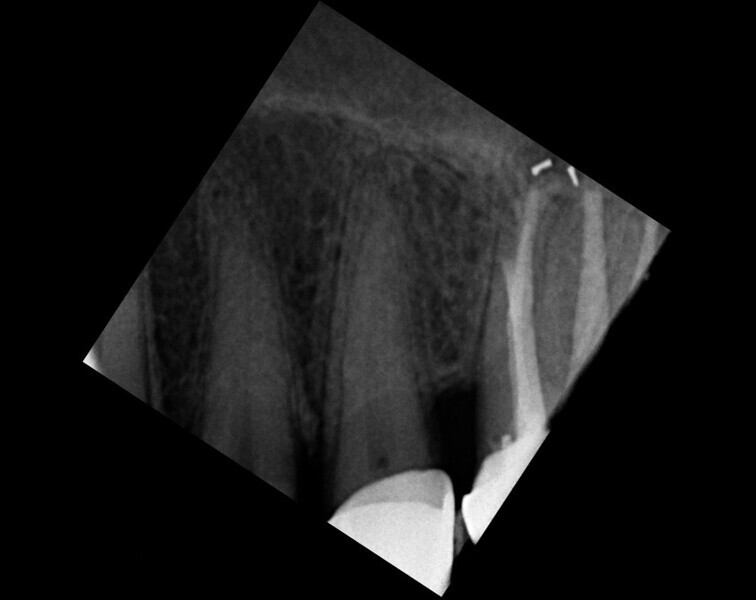

Maxillary sinus and root canal therapy complications